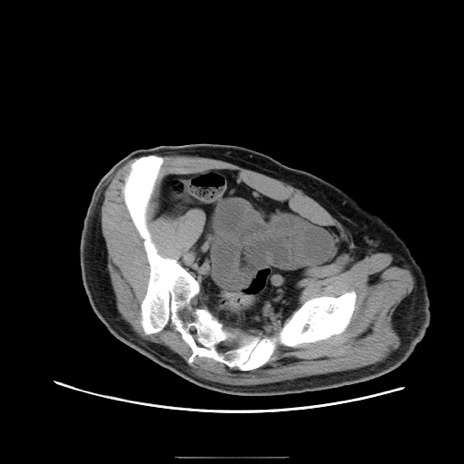

症例22(横断像)

【症例】50歳代男性

【主訴】腹痛

【現病歴】AVMからの被殻出血のため回復期リハ病棟入院中。 本日午後3時頃急に下腹部痛が出現した。

【既往歴】AVM、被殻出血、虫垂炎、高血圧

【身体所見】意識晴明、左半身不全麻痺、会話の理解は良好、36.5°C、腹部:膨隆、全体に板状硬、下腹部正中に圧痛点あり、反跳痛-、筋性防御不明、右下腹部にope scar

【データ】WBC 9400、CRP 0.06